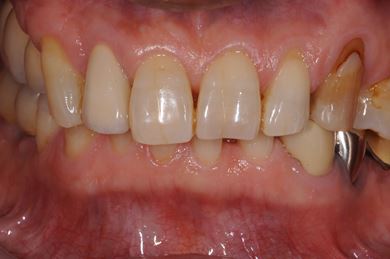

インプラントの症例写真 IMPLANT

骨再生インプラント治療+セラミック治療

| 性別/年齢 | 男性 / 60歳 | ||||||||||||||||||||||||||||||||

| 主訴 | 右上奥歯が動いて痛みがある。 | ||||||||||||||||||||||||||||||||

| 治療内容 | インプラント5本(サイナスリフト、GBR)、ハイブリッドセラミッククラウン5本、メタルボンドセラミッククラウン1本(メタルボンド用土台1本)、ハイブリッドセラミックインレー、遊離歯肉移植手術 | ||||||||||||||||||||||||||||||||

| 治療期間 | 1年7ヶ月 |